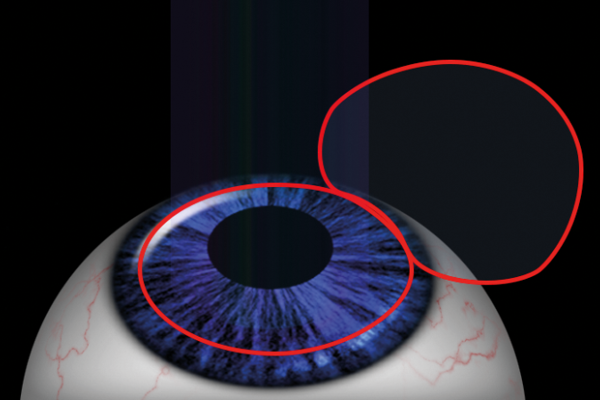

Laser corneal refractive procedures – a review